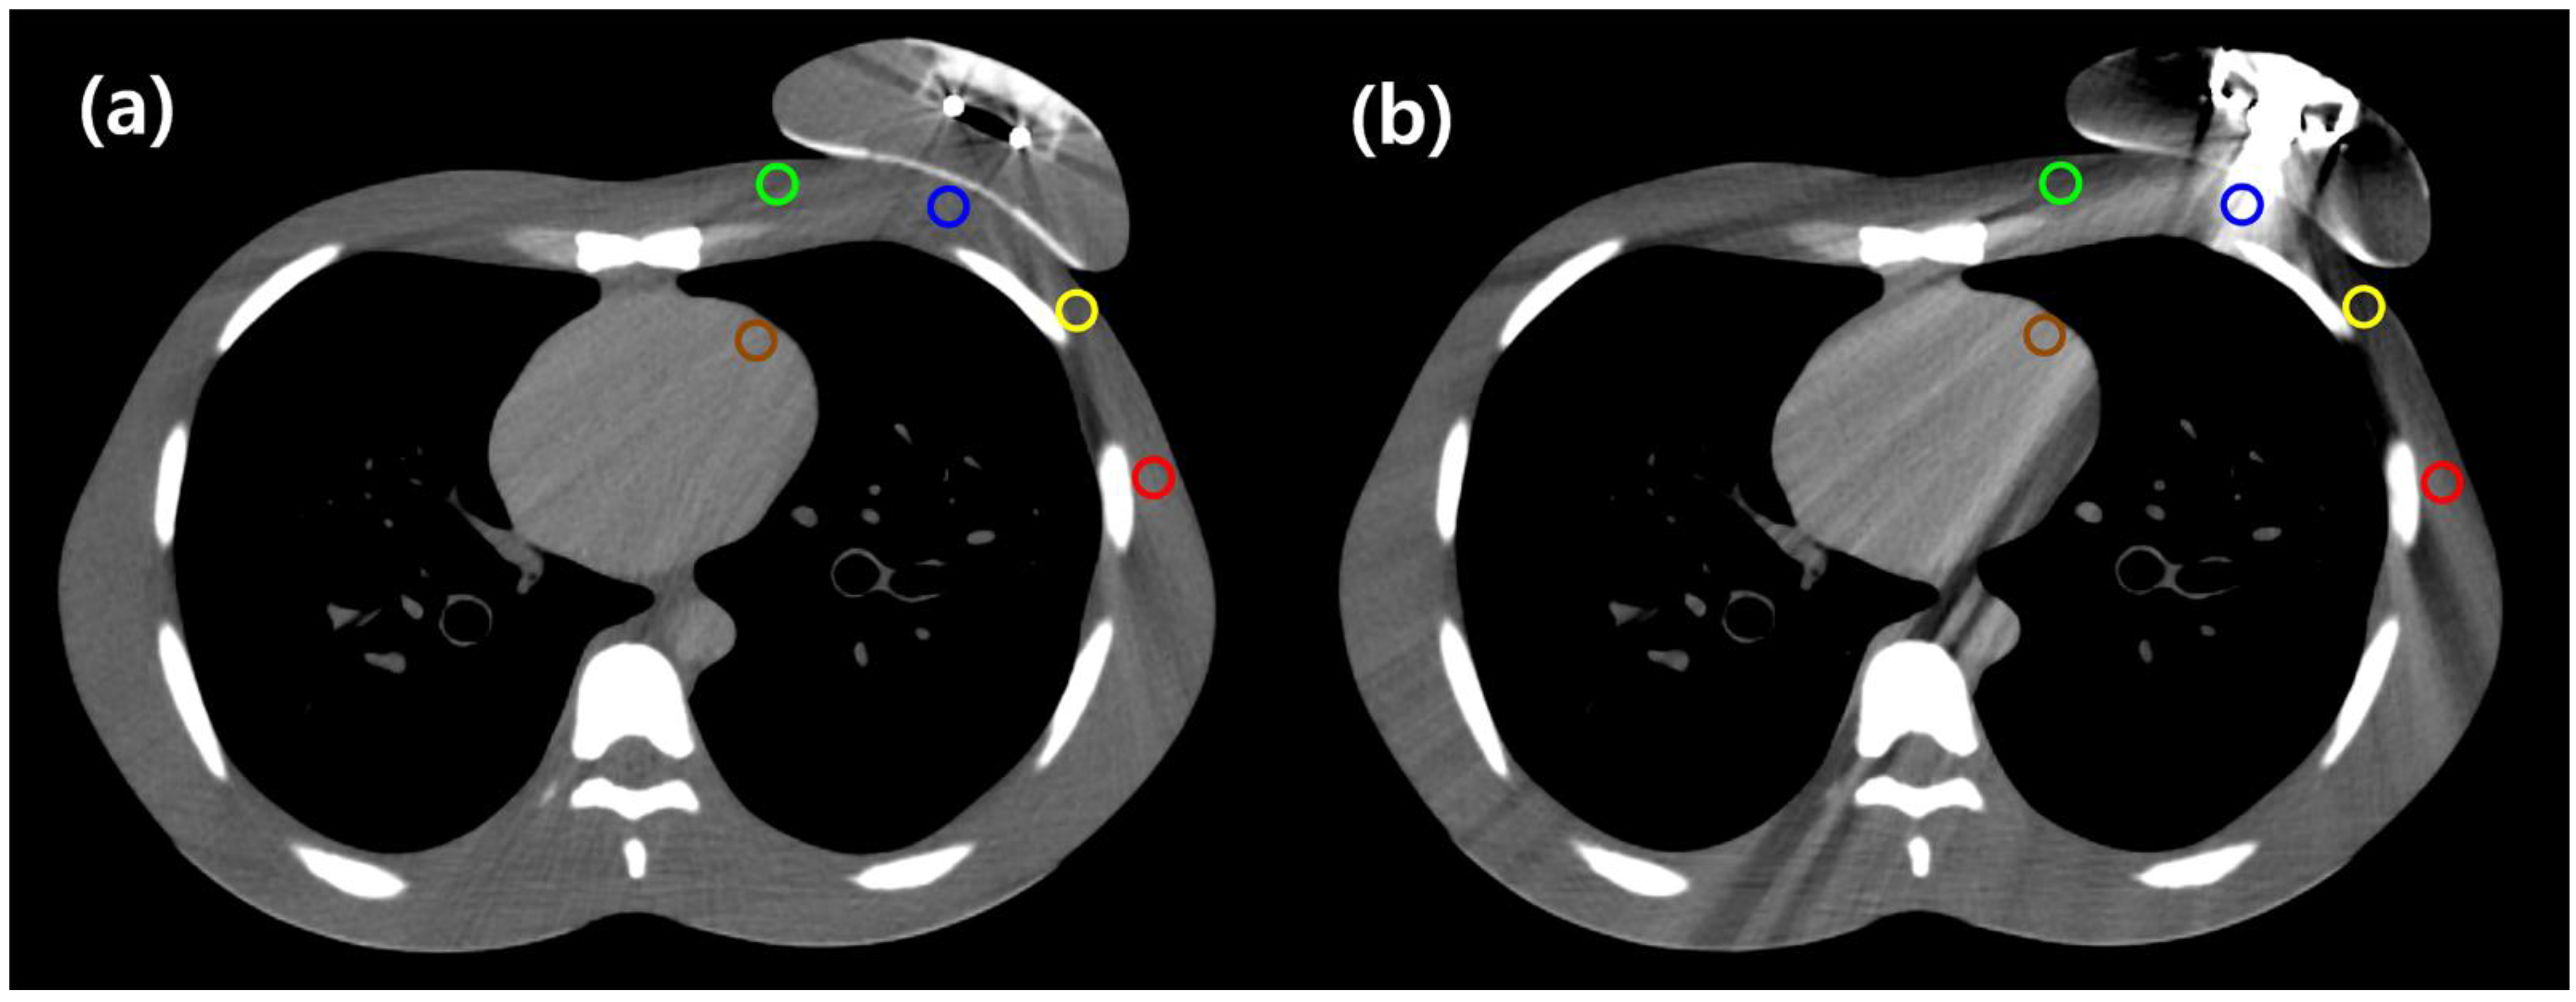

2.4. Computed Tomography Image Analysis

| Points of the Reference ROIs | RFID Port | Metallic Port | ||||

|---|---|---|---|---|---|---|

| Averaged HU | Averaged HU Difference | p-Value | Averaged HU | Averaged HU Difference | p-Value | |

| A (central chest wall) | −2.73 | −18.33 | 0.043 | 118.57 | −139.63 | 0.007 |

| B (medial chest wall) | −19.36 | 8.17 | 0.028 | −34.62 | 23.43 | 0.017 |

| C (lateral chest wall) | −37.36 | 14.93 | 0.028 | −74.37 | 51.94 | 0.005 |

| D (axilla) | −0.92 | −15.14 | 0.005 | −12.32 | −3.74 | 0.169 |

| E (left anterior descending artery) | 32.41 | −2.86 | 0.059 | 44.71 | −15.16 | 0.005 |